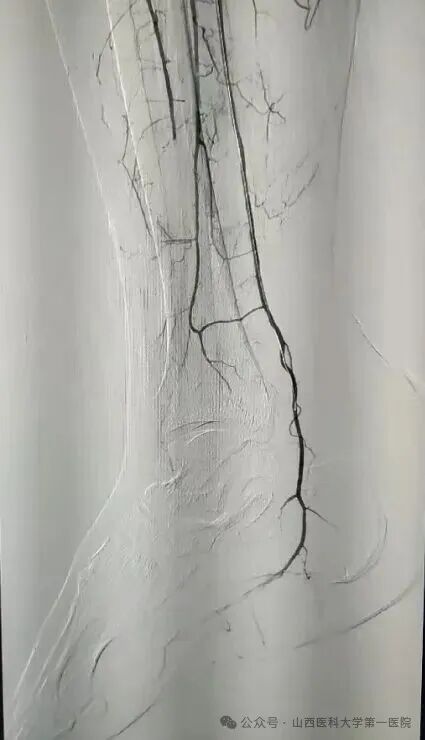

52岁王先生有长期高血压、糖尿病史,且未规范治疗控制,长期吸烟饮酒,饮酒量每日1斤左右,近年来逐渐出现间歇性跛行症状。10月20日凌晨,王先生突发右下肢发冷疼痛,当地医院下肢血管超声提示右侧髂动脉、股总动脉、腘动脉闭塞,紧急转诊至山医大一院血管外科。入院时患者右足发绀、皮温差,右足运动感觉明显减退,患侧股动脉、腘动脉、胫后动脉、足背动脉均无法触及搏动,这种急性髂股动脉血栓形成病情十分危急,死亡率40%以上,随时面临截肢与生命危险。

患者的全身状况同样堪忧,心肝肾功能异常,感染指标显著升高,“必须立刻打通血管,同时兼顾全身多器官的保护,既要保命,更要尽最大努力保肢,守护患者的生活尊严。”王贵明主任第一时间带领团队制定救治方案。为患者紧急实施了右髂动脉覆膜支架植入、球囊扩张成形及机械血栓清除等手术,成功恢复下肢血流。然而术后危机接踵而至:患者出现右小腿骨筋膜室综合征,骨科贾二龙主任医师紧急会诊后为其施行筋膜切开减压及负压封闭引流术;术后患者转入ICU,又相继出现急性肾衰竭、严重低蛋白血症、电解质紊乱、重度营养不良、发热及急性心衰等多重挑战,重症医学科与血管外科密切配合研判病情,通过抗凝、抗感染、营养支持、纠正心衰、连续性血液净化等一系列综合治疗,患者病情逐渐平稳。两周后转回普通病房,但肾功能仍未恢复。王贵明、马宏刚、刘唯棕组织全院大会诊,围绕透析管理、心功能维护、骨筋膜室综合征术后康复等制定后续方案。在肾内科、心血管内科、临床营养科等科室的共同配合下,患者全身状况日渐稳定。